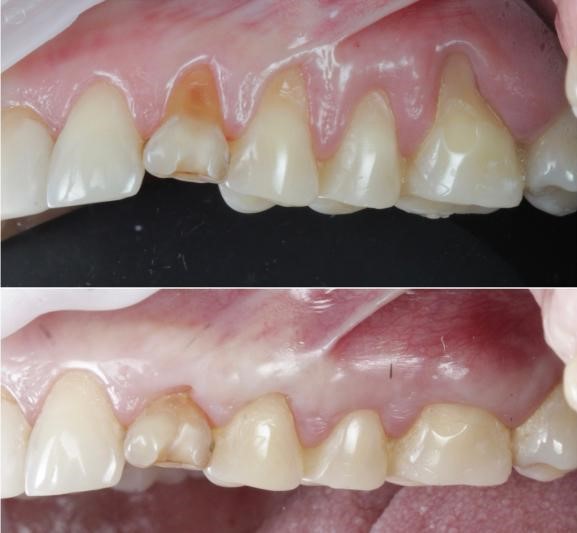

Сравните клык и соседний зуб, например

Иногда вообще странные истории происходят

На приём довольно часто приходят совсем молоденькие девушки, лет по 20–25 лет, у которых зубы стоят достаточно ровно и с ними в целом всё в порядке. Жевательные вообще почти идеально выглядят. А передняя группа зубов, с клыка по клык, стирается очень сильно, как будто их хозяйки уже разменяли шестой десяток. Так, конечно, быть не должно, и это звоночек о том, что действовать нужно срочно. А именно — убирать рецессии и разбираться с прикусом.